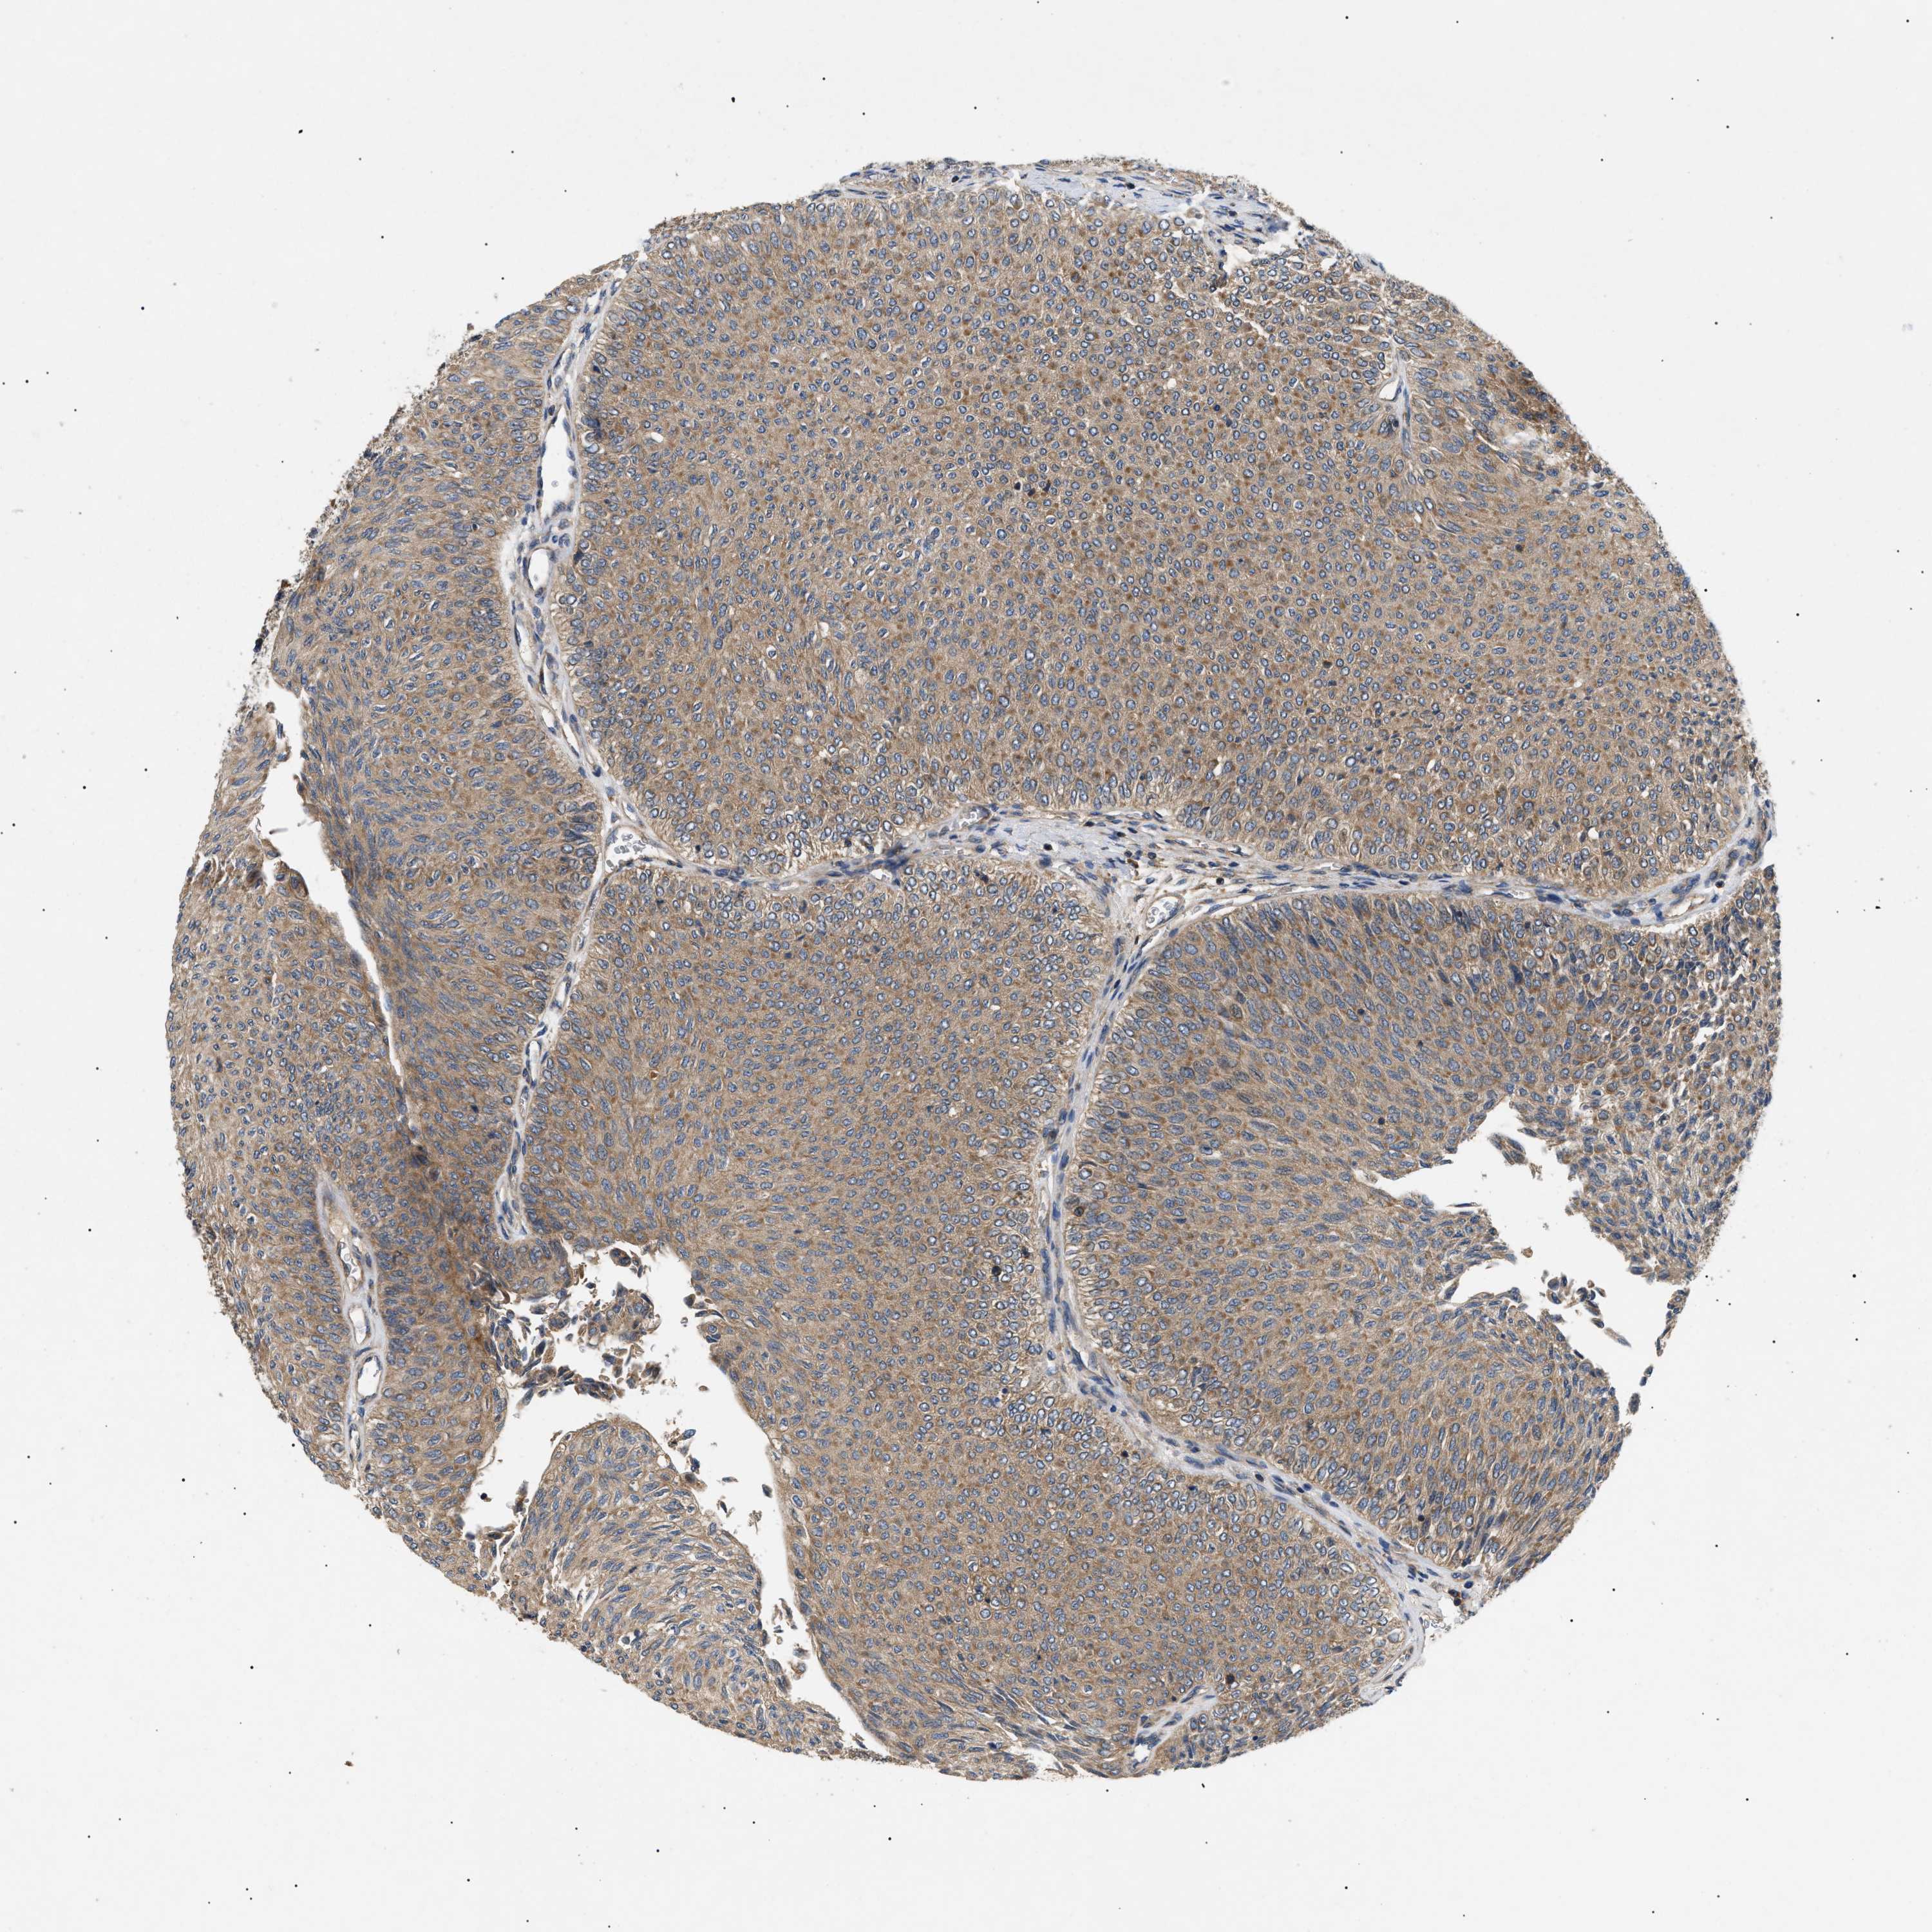

UROTHELIAL CANCER - Protein expressioni

A mouse-over function shows sample information and annotation data. Click on an image to view it in a full screen mode. Samples can be filtered based on level of antibody staining by selecting one or several of the following categories: high, medium, low and not detected. The assay and annotation is described here.

Note that samples used for immunohistochemistry by the Human Protein Atlas do not correspond to samples in the TCGA dataset.

Antibody stainingi

Antibody staining in the annotated cell types in the current human tissue is reported as not detected, low, medium, or high, based on conventional immunohistochemistry profiling in selected tissues. This score is based on the combination of the staining intensity and fraction of stained cells.

Each image is clickable and will lead to virtual microscopy that enables deeper exploration of all samples and also displays staining intensity scores, fraction scores and subcellular localization as well as patient and tissue information for each sample.

Antibody HPA016745

Staining

High

Medium

Low

Not detected

Intensity

Strong

Moderate

Weak

Negative

Quantity

>75%

75%-25%

<25%

None

Location

Nuclear

Cytoplasmic/membranous

Cytoplasmic/membranous,nuclear

Urothelial carcinoma, Low grade

Urothelial carcinoma, High grade